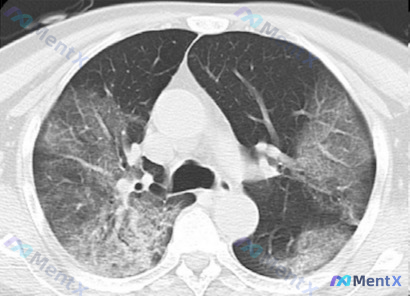

整理到一张胸部CT肺窗的横断面影像资料,先给大家放核心表现: - 双侧肺野广泛密度增高影,对称性分布 - 大范围磨玻璃影(GGO),背景下仍可见肺纹理穿行 - 双肺下叶及后部有多发斑片状实变影,与GGO混合存在 - GGO区域可见细网格影及小叶间隔增厚 - 气管主支气管通畅,无明显胸水/气胸/纵隔大...